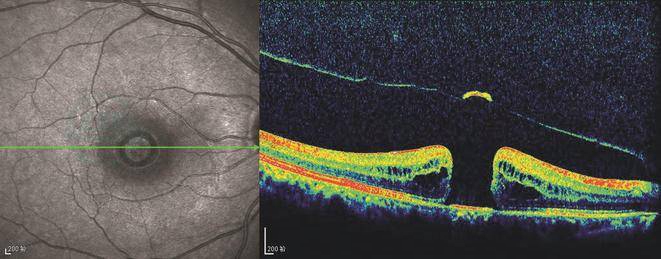

OCT检查是黄斑裂孔诊断的金标准。外伤性黄斑裂孔伴水肿的OCT图像特征为黄斑中心光带中断缺失及裂孔形成(图2)。图像特征与特发性黄斑裂孔图像特征相似,可表现为外伤性黄斑裂孔伴神经上皮水肿及脱离、神经上皮层变薄、神经上皮脱离等。

图2 黄斑裂孔OTC表现